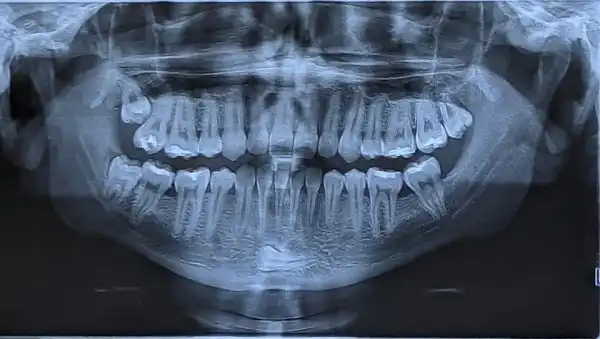

Рентген моих зубом примерно 2 месяца назад